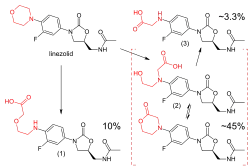

Linezolid is metabolized in the liver, by oxidation of the morpholine ring, without involvement of the cytochrome P450 system. This metabolic pathway leads to two major inactive metabolites (which each account for around 45% and 10% of an excreted dose at steady state), one minor metabolite, and several trace metabolites, none of which accounts for more than 1% of an excreted dose.[105] Clearance of linezolid varies with age and gender; it is fastest in children (which accounts for the shorter half-life), and appears to be 20% lower in women than in men.[8][105][106] There is a strong correlation between linezolid clearance and creatinine clearance.[107]